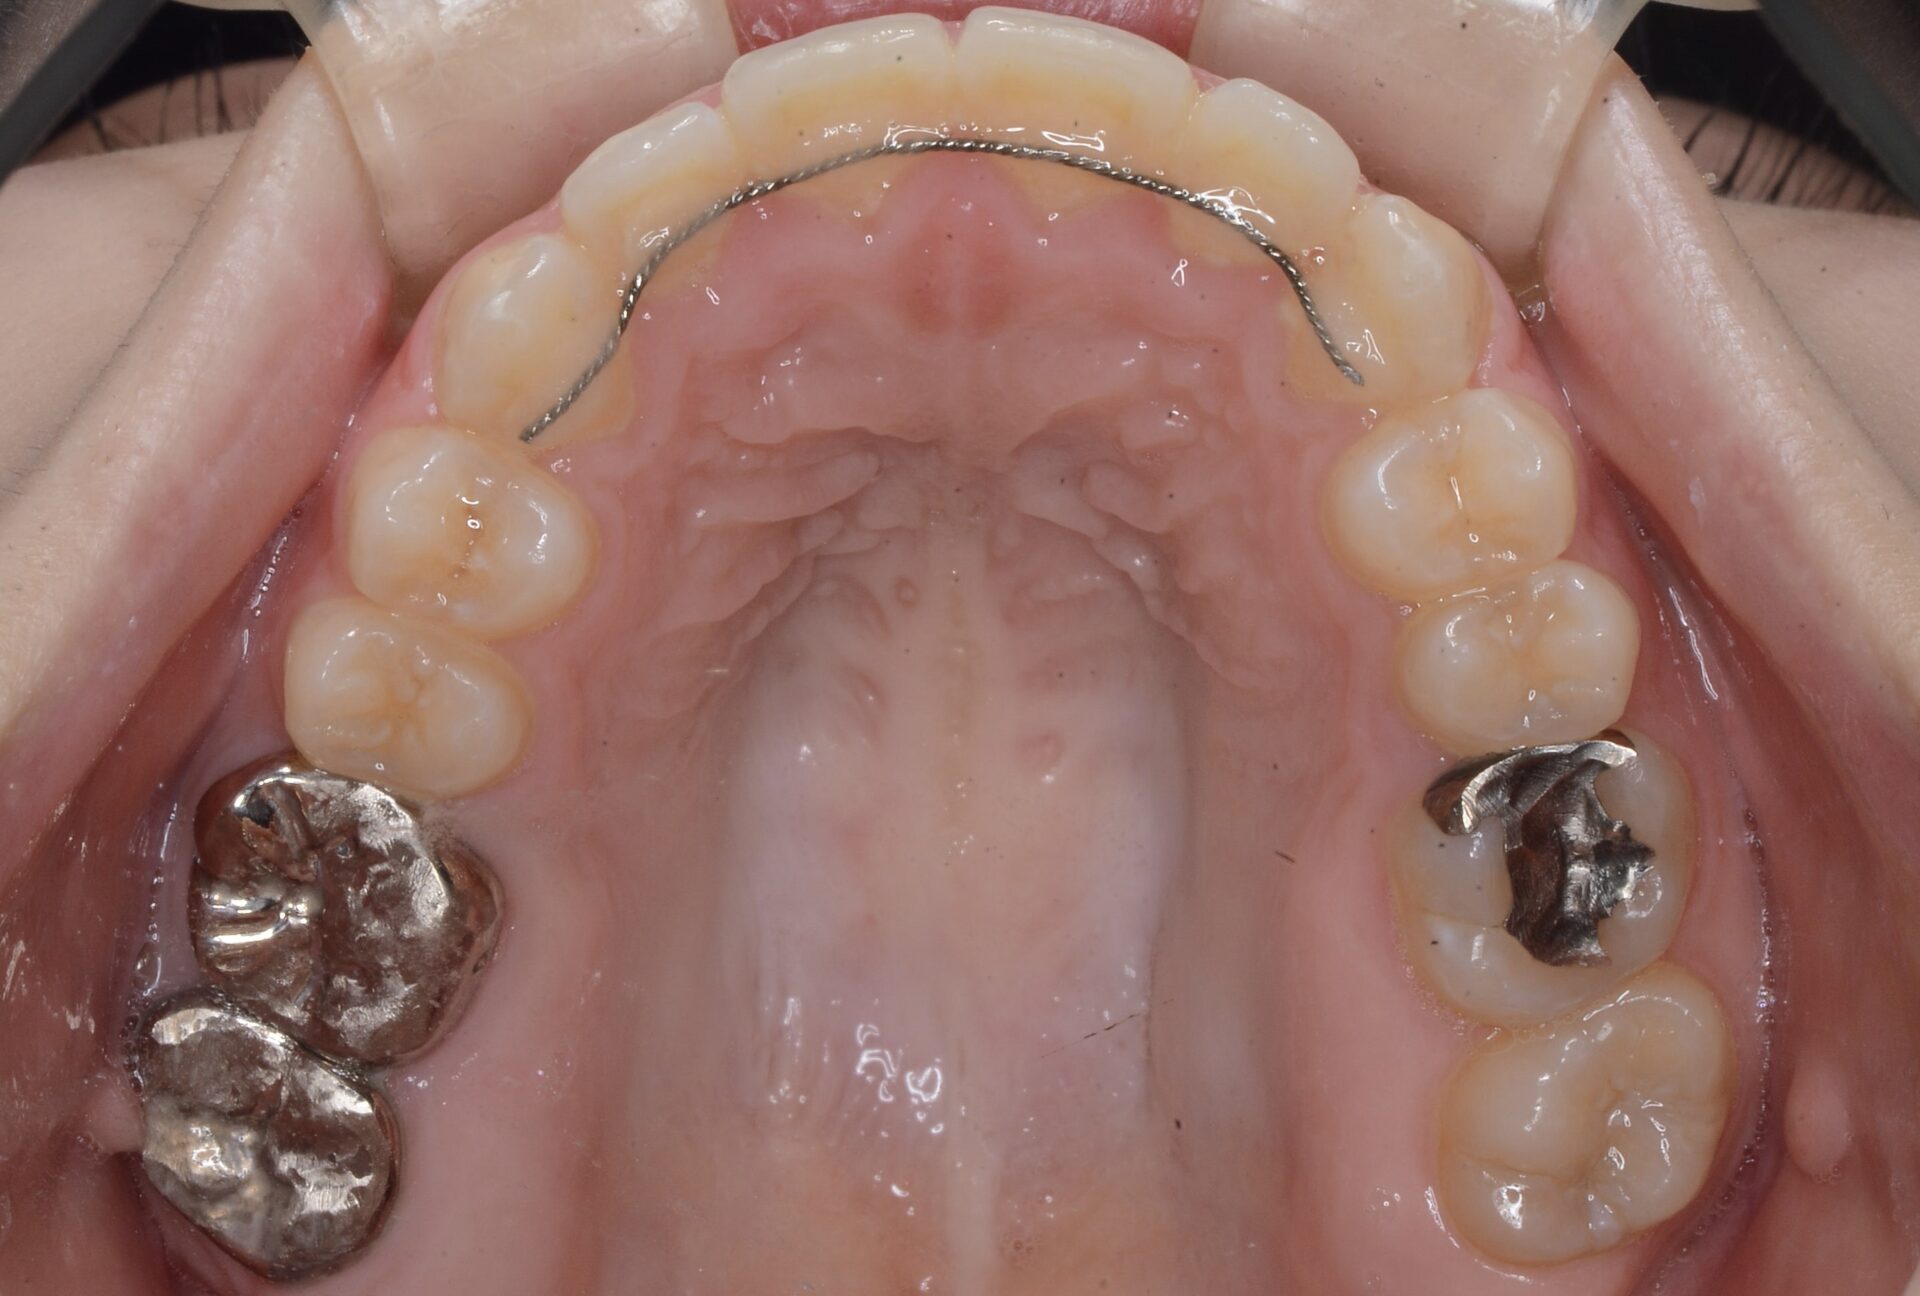

メインテナンス時(上顎)

20代前半で歯の位置はまだ変化すること、先欠部の歯槽骨が未熟であったことからインプラントではなく、大臼歯を利用したジルコニアシングルウイングの詰め物で対応した。